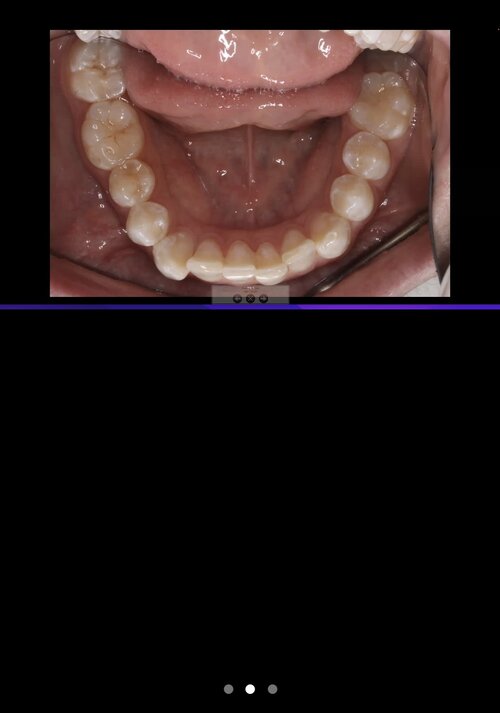

I have been recommended by the orthodontist to get my back left molar removed and potentially my wisdom teeth. He then said i should get 3 years of braces and some other shit. I feel like this is all bull shit, and he just wants to extort my parents' money. He said that because my back left molar is not coming through, my jaw could not be developing, but this contradicts everything I have seen on here with teeth extractions leading to recession. Could someone please help me